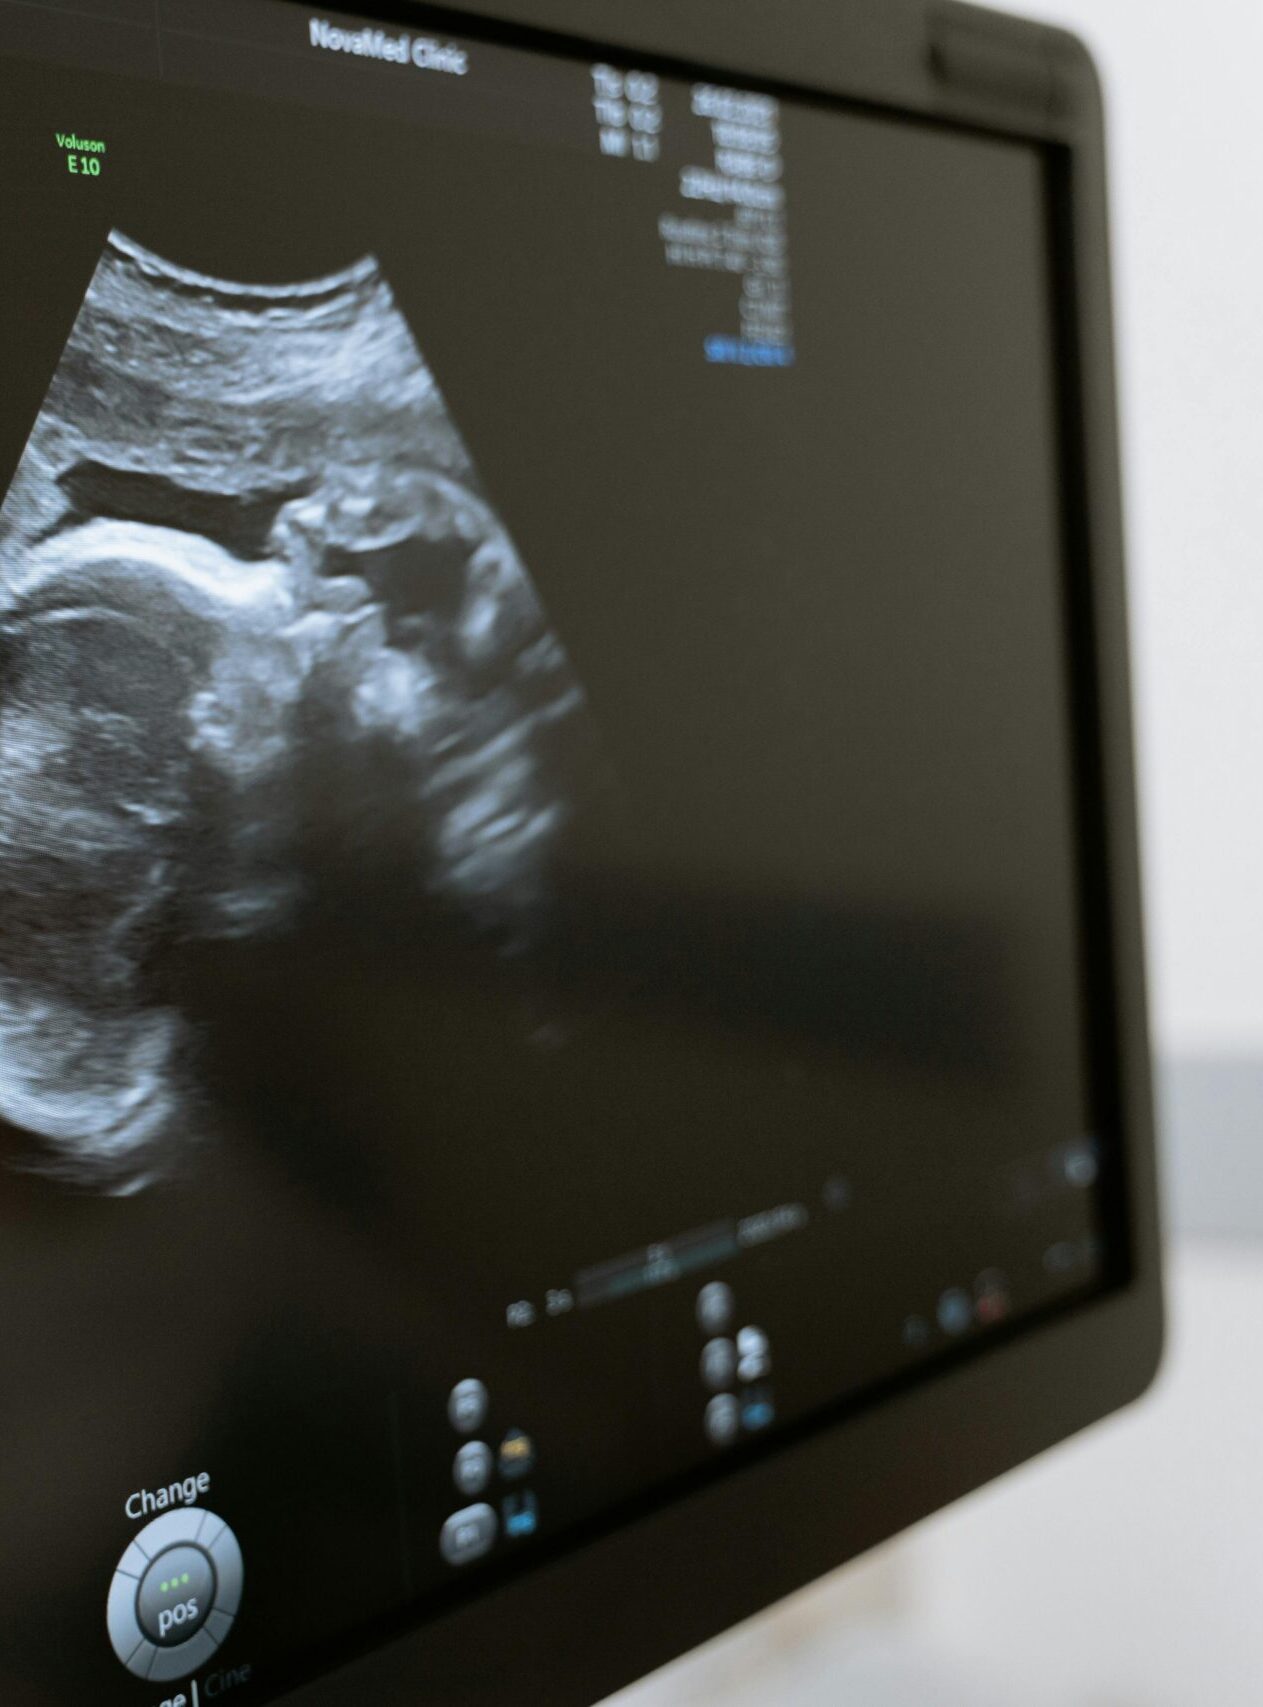

La misurazione della translucenza nucale (NT) è un esame ecografico fondamentale tra le ecografie ostetriche, utilizzato per valutare la raccolta di fluido presente nella regione cervicale fetale. Questo parametro consente di stimare il rischio di cromosomopatie fetali, come la trisomia 21 o la trisomia 18.

Come si Svolge l’Esame

- Si esegue a vescica vuota con una sonda addominale.

- Il paziente viene posizionato disteso su un lettino, e il medico applica un gel ecografico sull’addome, muovendo la sonda per acquisire le immagini.

- L’esame è indolore, rapido e utilizza onde sonore ad alta frequenza, innocue e prive di radiazioni.

Al termine, il referto con le immagini viene consegnato immediatamente.